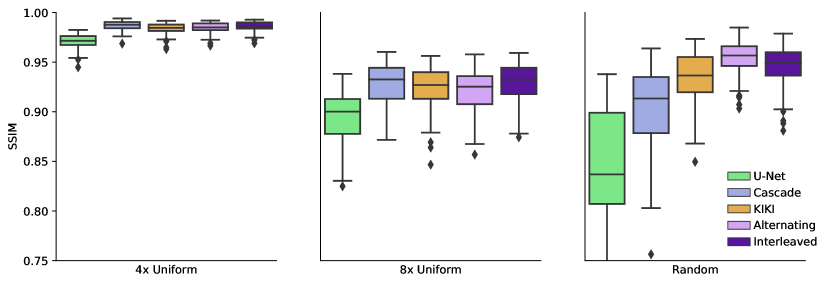

Fig. 4 reports reconstruction quality statistics for all four types of simulations described in Section 4.1.1: motion, noise, undersampling, and motion combined with undersampling. The Interleaved and Alternating architectures outperform the baseline architectures for nearly every task and subject. Across all tasks and nearly all subjects, the Interleaved and Alternating architectures are quite similar in numerical performance. Sample image reconstructions for the motion, motion with undersampling and denoising tasks are shown in Figs. 5-7. Qualitatively, for each task, the Frequency network provides a blurry version of the ground truth image. The Image network provides a reconstruction which effectively removes ‘background’ effects but has limited success in correcting these artifacts within the image. In contrast, the Interleaved and Alternating networks provide sharper, high-quality reconstructions across all tasks. Further, the frequency space reconstructions provided by those networks appear the most faithful to the ground truth frequency data.

4.2.1 Results

Fig. 8 reports statistics for U-Net, CascadeNet, KIKI-net, Joint and Alternating networks. Fig. 9 provides sample image reconstructions. Interleaved and Alternating networks perform comparably to other state of the art methods on the simpler uniform undersampling tasks and outperform the state of the art methods on the more complex random undersampling task.